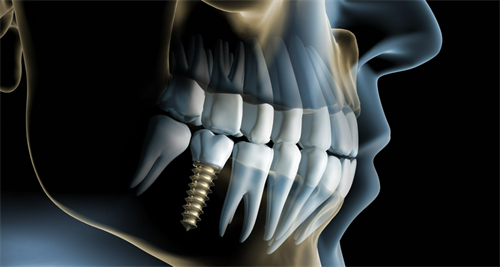

国产种植牙:5280元起/颗

韩国登腾种植牙:6000元起/颗

韩国奥齿泰种植牙:6780元起/颗

美国皓圣种植牙:8900元起/颗

德国费亚丹种植牙:10000元起/颗

瑞士ITI种植牙:11000元起/颗

瑞典诺贝尔种植牙:11600元起/颗

半口种植牙:50000元起

全口种植牙:98000元起